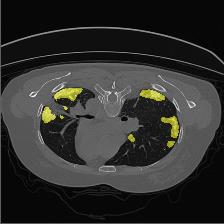

Medical image segmentation is one of the most fundamental tasks concerning medical information analysis. Various solutions have been proposed so far, including many deep learning-based techniques, such as U-Net, FC-DenseNet, etc. However, high-precision medical image segmentation remains a highly challenging task due to the existence of inherent magnification and distortion in medical images as well as the presence of lesions with similar density to normal tissues. In this paper, we propose TFCNs (Transformers for Fully Convolutional denseNets) to tackle the problem by introducing ResLinear-Transformer (RL-Transformer) and Convolutional Linear Attention Block (CLAB) to FC-DenseNet. TFCNs is not only able to utilize more latent information from the CT images for feature extraction, but also can capture and disseminate semantic features and filter non-semantic features more effectively through the CLAB module. Our experimental results show that TFCNs can achieve state-of-the-art performance with dice scores of 83.72\% on the Synapse dataset. In addition, we evaluate the robustness of TFCNs for lesion area effects on the COVID-19 public datasets. The Python code will be made publicly available on https://github.com/HUANGLIZI/TFCNs.